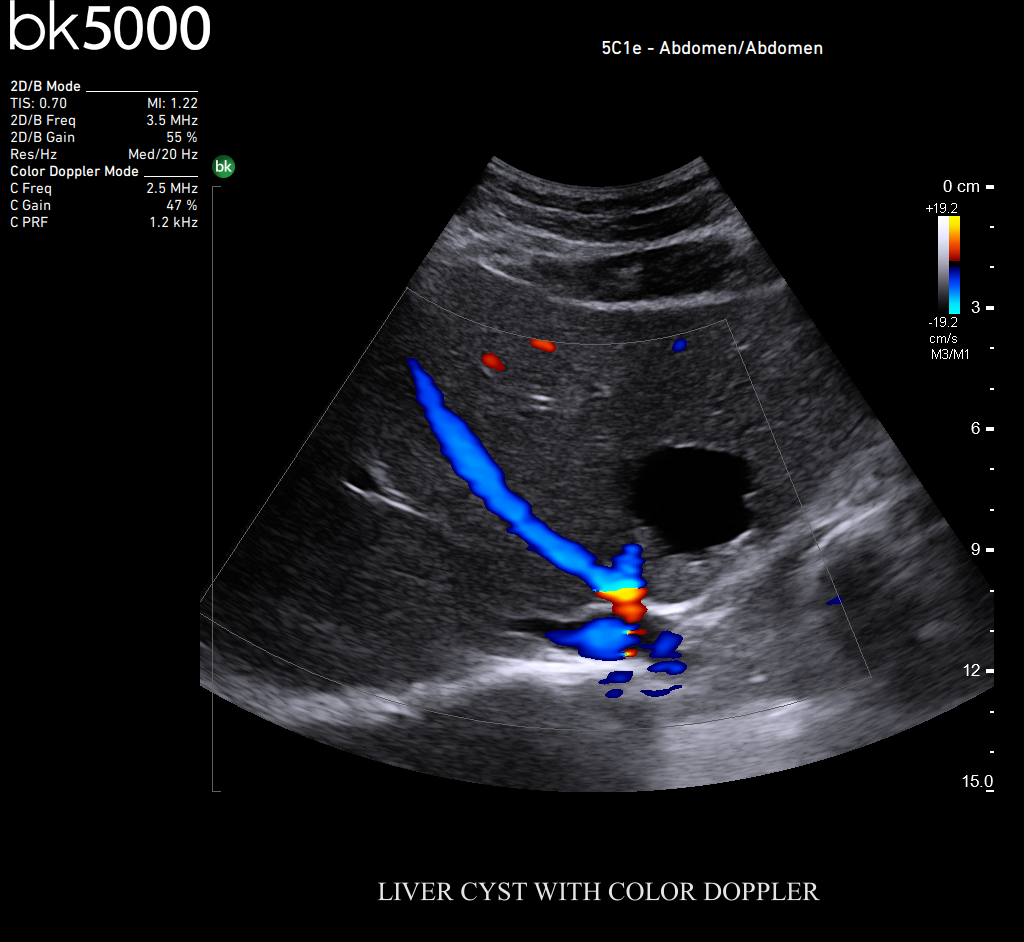

You know what you need, and you need it fast. That’s why the bk5000 is designed to deliver the high resolution images you count on quickly and efficiently. Whether you’re identifying margins of a lesion or making a general assessment of an area of interest, the bk5000 has the power and performance to meet your needs on your terms.

From the simplest diagnostic imaging to the most critical interventional procedures, every clinical situation has its own set of unique challenges. The bk5000 offers a full suite of innovative technologies and advanced controls and adjustments to help you achieve the best possible image quality, across many applications.